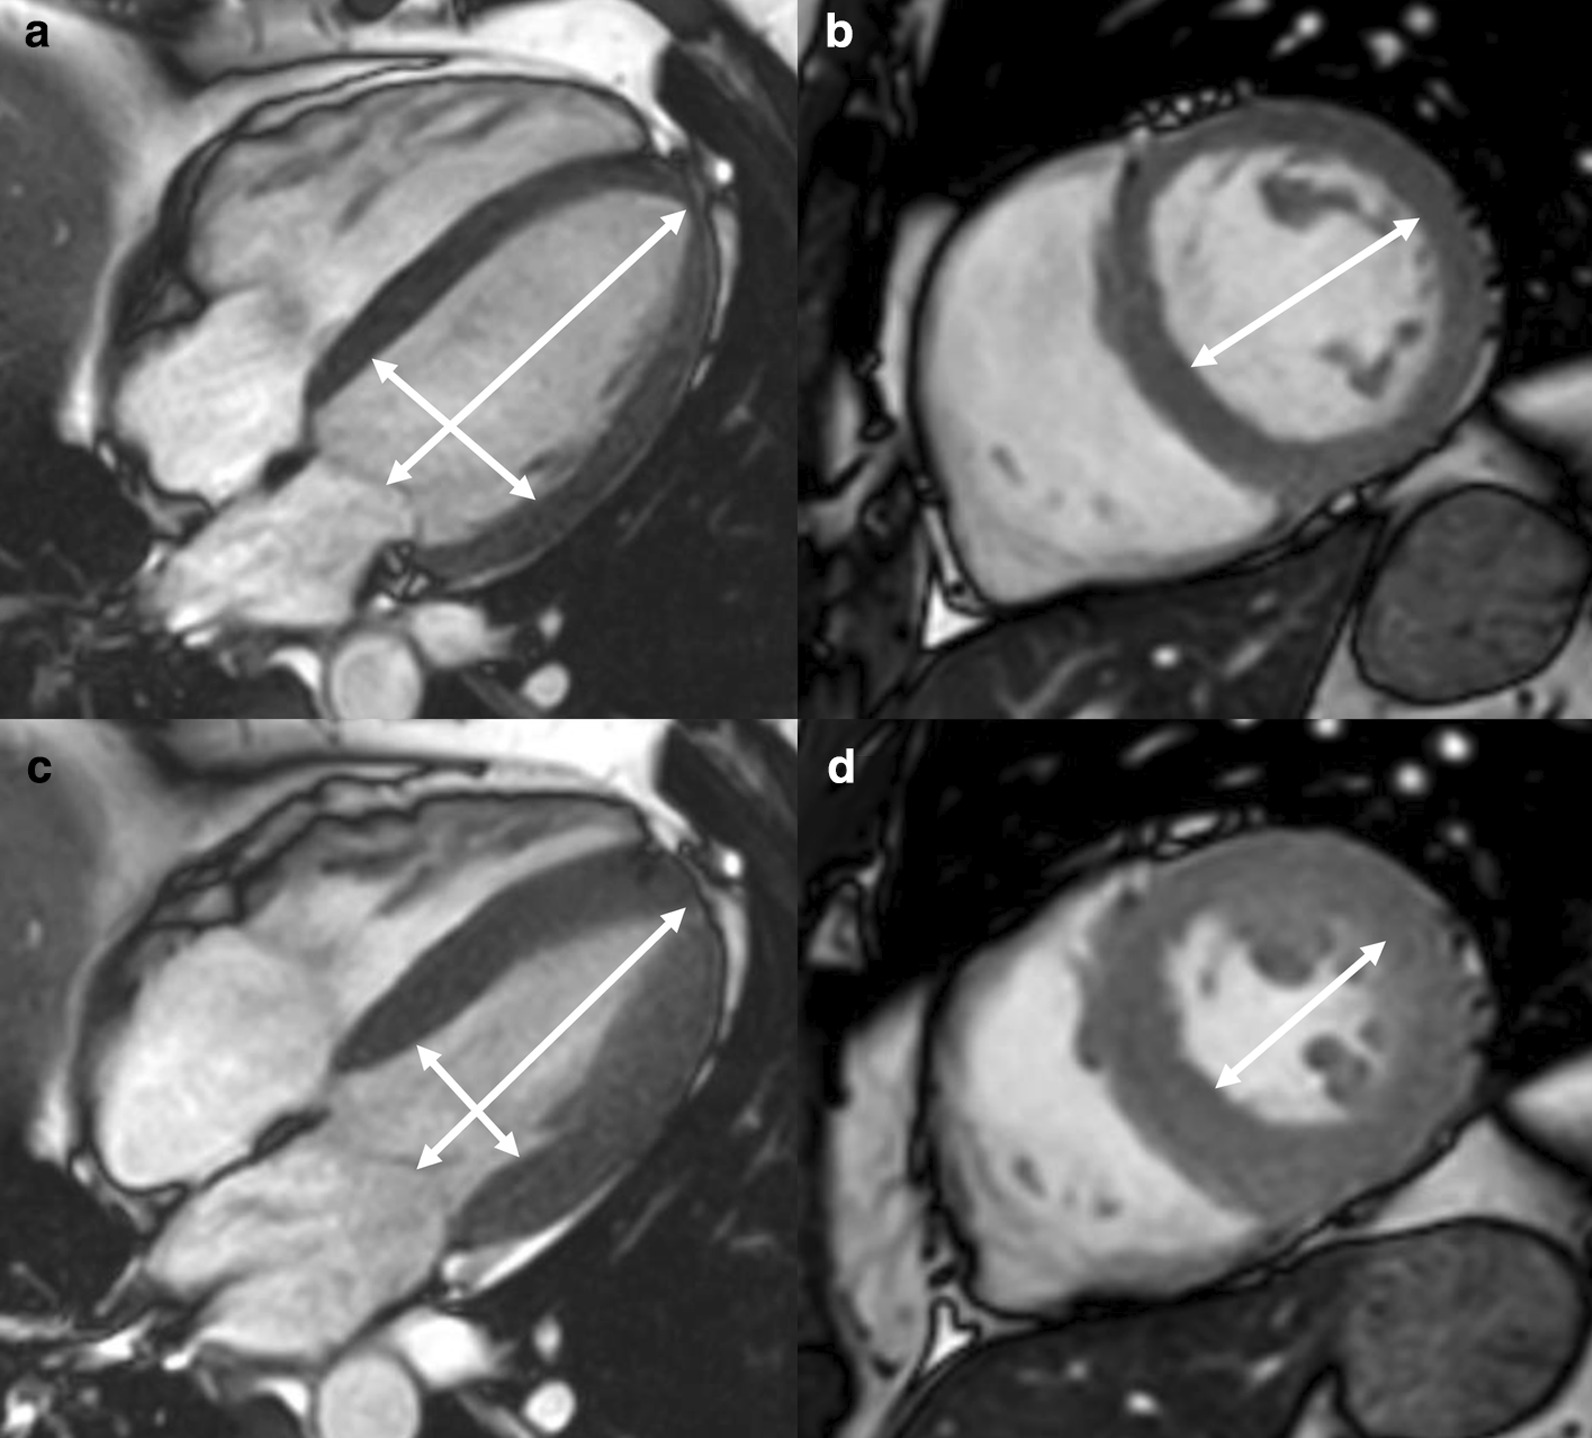

Measurements of LV diameter obtained on cine bSSFP images at diastole and systole on a 4 chamber view and short axis view are shown in Fig. 2.

Fig. 2.

Measurements of LV diameters obtained on cine bSSFP images during diastole (a, b) and systole (c, d) on the 4 chamber view (a, c) and short axis view (b, d). The longitudinal diameter of the LV was measured on the 4 chamber view as the distance between the mitral valve plane and the LV apex (a, c). On the 4 chamber view the transverse diameter was defined as the distance between the septum and the lateral wall at the basal level [18]. On the short axis view the transverse diameter was obtained at the level of the basal papillary muscles (b, d) [15]